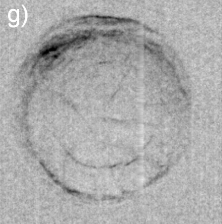

Dilute concentrations of precipitates without cores have also been observed, Figs. 3(e) and 3(f), as well as clinical cases of cataract with well-defined Y-sutures but with no distinct amounts of precipitates. In these cases, which correspond to 60% of the analyzed cases, there are significant scattering at the suture marks that can be generated either by local compaction of fiber cells or accumulation of precipitates along the marks, as for instance in Figs. 3(g) through 3(l). Refraction images show the extension of compaction areas while diffuse-scattering images can revel the presence or not of precipitates at the sutures. Absorption images (center of the analyzer window) provide essentially the same information of diffuse-scattering ones.